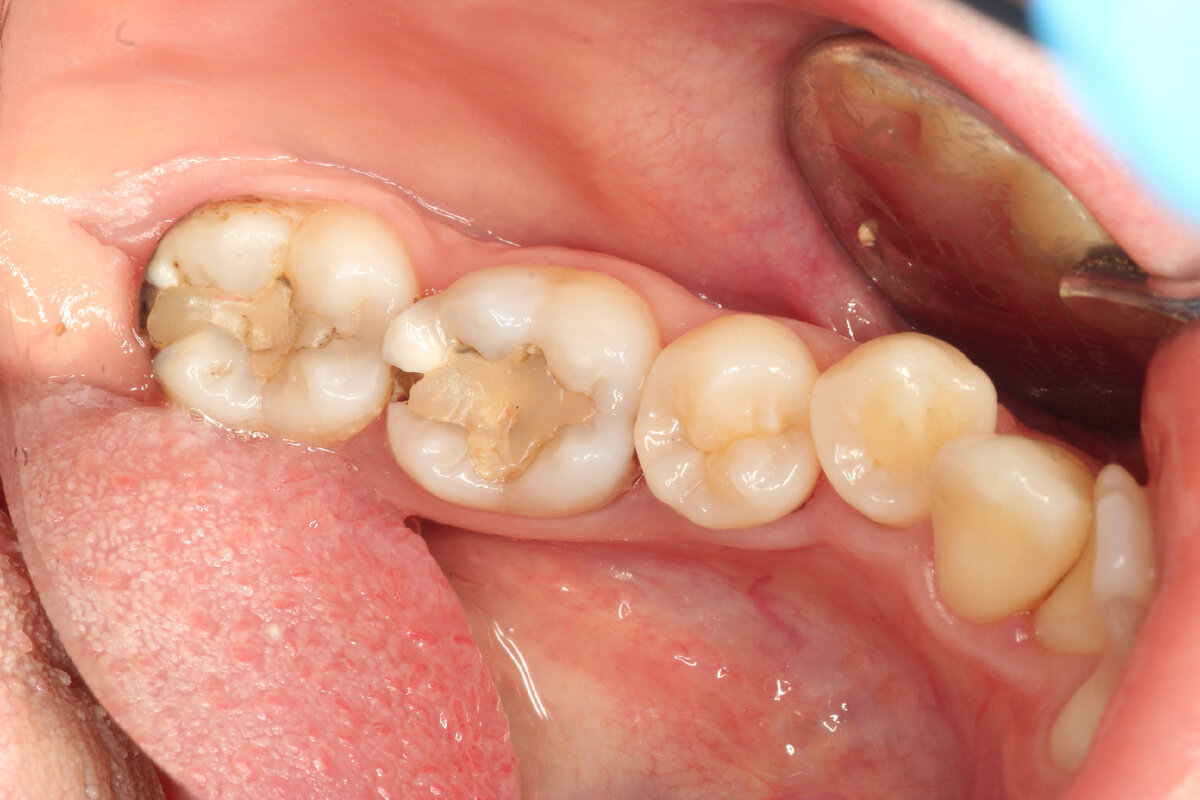

Вычистили весь кариес. Разрушение оказалось довольно глубоким, еще чуть-чуть и пришлось бы лечить зубик в каналах. Из-за того, что позади стоящий зуб еще не прорезался, пришлось прижимать металлическую матрицу, которая формирует выпуклую стенку зуба, вручную

Финальное фото, отпускаем счастливого пациента домой